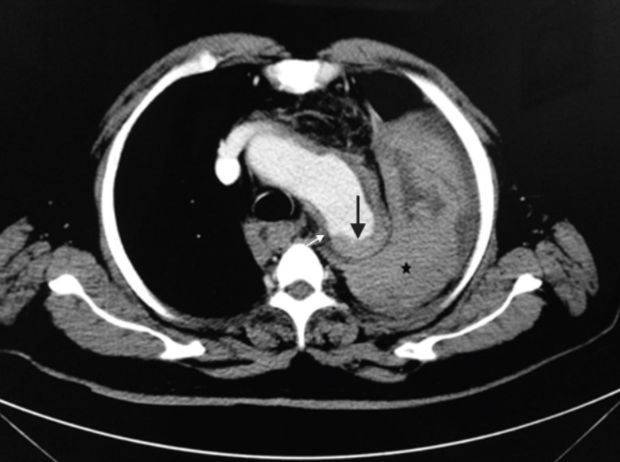

Bác sĩ Nguyễn Minh Đức – Giảng viên Trường Đại học Y Phạm Ngọc Thạch (TPHCM), trước đó, bệnh nhân đến bệnh viện khám do có các triệu chứng của rối loạn tiêu hóa. Tuy nhiên, trong quá trình khám bệnh, bác sĩ đã phát hiện bệnh nhân bị phình động mạch chủ ngực, kích thước lên tới 50mm.

Bác sĩ tư vấn bệnh nhân can thiệp điều trị đặt stent graft ngay vì có nguy cơ vỡ túi phình động mạch chủ ngực nhưng bệnh nhân mong muốn là quay trở lại Úc điều trị. Dù được bác sĩ giải thích về những nguy cơ có thể xảy ra vỡ túi phình, thậm chí có thể nguy kịch tới tính mạng nhưng bệnh nhân vẫn nhất quyết từ chối điều trị và đặt vé máy bay về Úc.

Tuy nhiên, chưa kịp bay thì ngay hôm sau, bệnh nhân đã phải nhập viện cấp cứu trong tình trạng hôn mê. Theo người nhà, người bệnh đã bất tỉnh sau một cú hắt xì. Qua kết quả chụp CT, bác sĩ xác định bệnh nhân bị vỡ túi phình, khiến người bệnh sốc và tử vong ngay sau đó.

Theo bác sĩ Đức, động mạch chủ là mạch máu lớn nhất trong cơ thể, xuất phát từ tim và đưa máu giàu oxy đến các cơ quan khác như ngực, bụng, tứ chi... Phình động mạch chủ ngực là tình trạng một đoạn động mạch chủ chạy qua ngực bị tổn thương, dần suy yếu, phình to ra.

Khi hắt hơi, người bệnh sẽ lấy hơi bụng đẩy lên, gây áp lực lên động mạch chủ ngực. Động mạch đang phình căng như bóng bay khi bị tác dụng lực sẽ rất dễ vỡ, dẫn đến chảy máu ồ ạt vào tim, phổi gây sốc và người bệnh có nguy cơ tử vong rất cao.